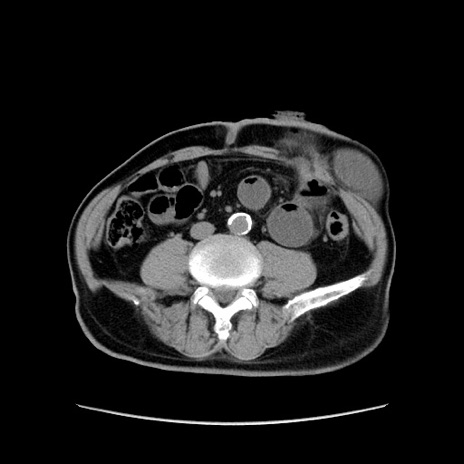

症例24(横断像)

【症例】80歳代男性

【主訴】左側腹部痛、嘔吐

【現病歴】本日早朝より左腹部に痛みあり。昼頃嘔吐認めたため、救急要請。

【既往歴】直腸癌(Mile手術)、胆摘

【身体所見】意識清明、BT 35.9℃、BP 221/93mmHg、SpO2 97%(RA) 、腹部:左ストーマ周囲に限局性の腹部膨隆あり。 膨隆部自発痛・圧痛あり・軟。

【データ】WBC 7700、CRP 0.09